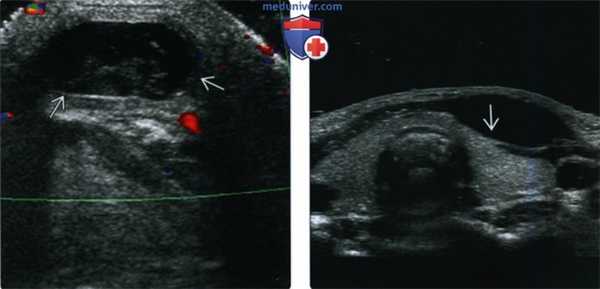

(Слева) На поперечной сонограмме в подкожных тканях визуализируется гипоэхогенное объемное образование с ровными краями, расположенное парамедианно справа, спереди от подподъязычных мышц. Образование было оперативно удалено, подтвердилась КЩЯП.

(Справа) На поперечной сонограмме у ребенка с подозрением на кисту щитоязычного протока в области предполагаемой локализации в нижних отделах шеи визуализируется щитовидная железа, имеющая нормальный вид (состоящая из двух долей). У всех пациентов, обследуемых на предмет КЩЯП, важно документально отразить наличие щитовидной железы в ожидаемом месте и отсутствие патологических изменений с ее стороны.

(Слева) УЗИ в поперечной плоскости у ребенка с вновь появившимся объемным образованием передних отделов шеи слева: визуализируется патологический гетерогенный очаг без признаков кровотока при цветовой допплерографии, но с выраженными эхогенными включениями, наличие которых позволяет заподозрить дермоид или рак в КЩЯП. При патоморфологическом исследовании подтвердилась киста, не осложненная кровоизлиянием, инфекцией, без признаков наличия злокачественной опухоли.

(Справа) УЗИ в поперечной плоскости у восьмилетнего ребенка: визуализируется типичная подподъязычная КЩЯП в виде анэхогенного объемного образования, расположенного парамедианно и обусловливающего легкое сдавливание левой доли щитовидной железы, в остальном выглядящей нормальной.